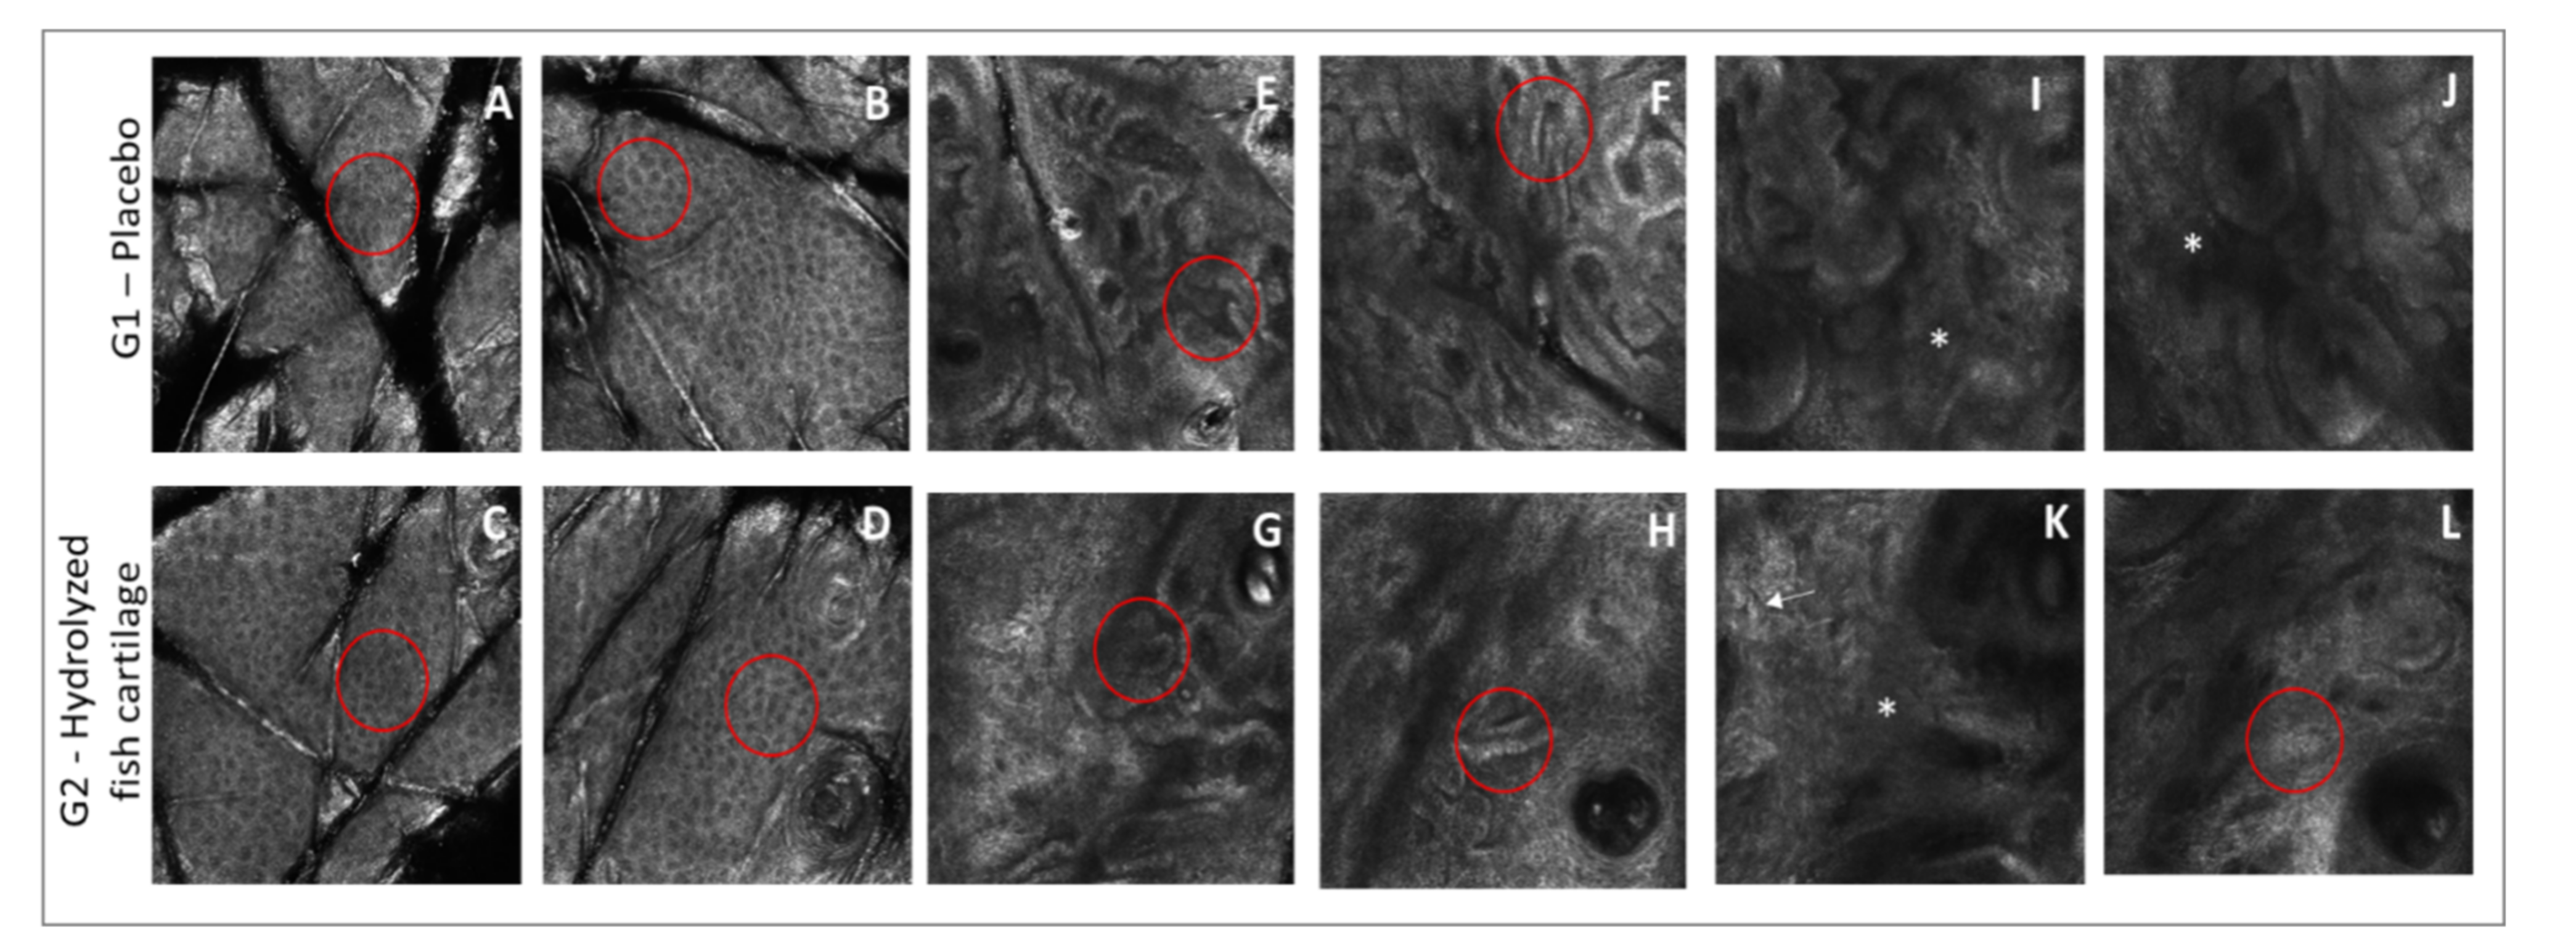

2.4. Morphological and Structural Skin Characteristics Determined by Reflectance Confocal Microscopy (RCM)

| Irregular honeycomb pattern | 67 | 33 | 0.0001 * | 83 | 33 | 0.0001 * |

| Low interkeratinocyte reflectance | 33 | 17 | 0.0138 * | 33 | 0 | 0.0001 * |

| Polycyclic papillary contours | 83 | 83 | 1.0000 | 67 | 67 | 1.0000 |

| Effacement of rete ridges | 17 | 17 | 1.0000 | 50 | 50 | 1.0000 |

| Coarse collagen structures | 67 | 67 | 1.0000 | 83 | 100 | 0.0001 * |

| Huddled collagen structures | 33 | 33 | 1.0000 | 17 | 0 | 0.0001 * |

| Curled bright structures Elastosis | 50 | 50 | 1.0000 | 83 | 67 | 0.0138 * |